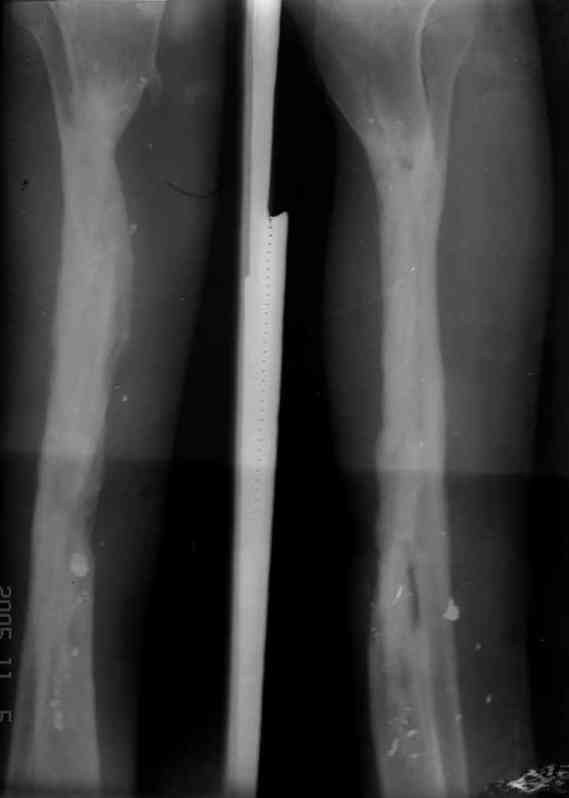

5. Ну и чтобы не быть голословным. Молодой человек подорвался на фугасе (Чечня, 2005 год). Свежие рентгенограммы:

Соответственно ожоги и дефект мягких тканей, переломы костей стопы и пр. Наложили аппарат

Илизарова (как придется), хирургически обработали и героически заживляли мягкие ткани с многочисленными кожными пластиками. В итоге через полгода я принял его вот таким:

Реализовал описанную выше методику, и в итоге вот что получилось. Высылаю лишь прямые проекции,

в боковых тоже всё в тему.

Очень пригодились карбоновые кольца (Джолдас -огромное спасибо, я твой должник!!!), поскольку остеопороз дистального отломка был просто невероятный. На цифровом рентгене с трудом угадывались контуры.

Рентген в процессе перемещения - внизу карбоновые кольца, тракция фрагмента спицами с упором.

внешний вид в аппарате - не завершающем этапе, сначала стопа тоже была фиксирована в аппарате.

Сейчас аппарат сняли, но случай ещё не завершенный.

Признаюсь честно, не совсем уверен в прочности консолидации на стыке косточек. Кроме того, укорочение в районе 6 см. Сейчас реабилитация - ходит опираясь на ногу с одним костылем.

Продолжение, видимо, будет... Возможно, будем удлинять.